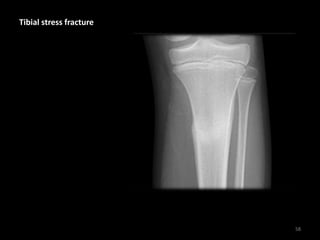

Tibial stress fracture

• Periosteal stress

reaction are signs of

stress injury (often not

present on the initial X-

ray)

• History of chronic pain

worsened by activity

59